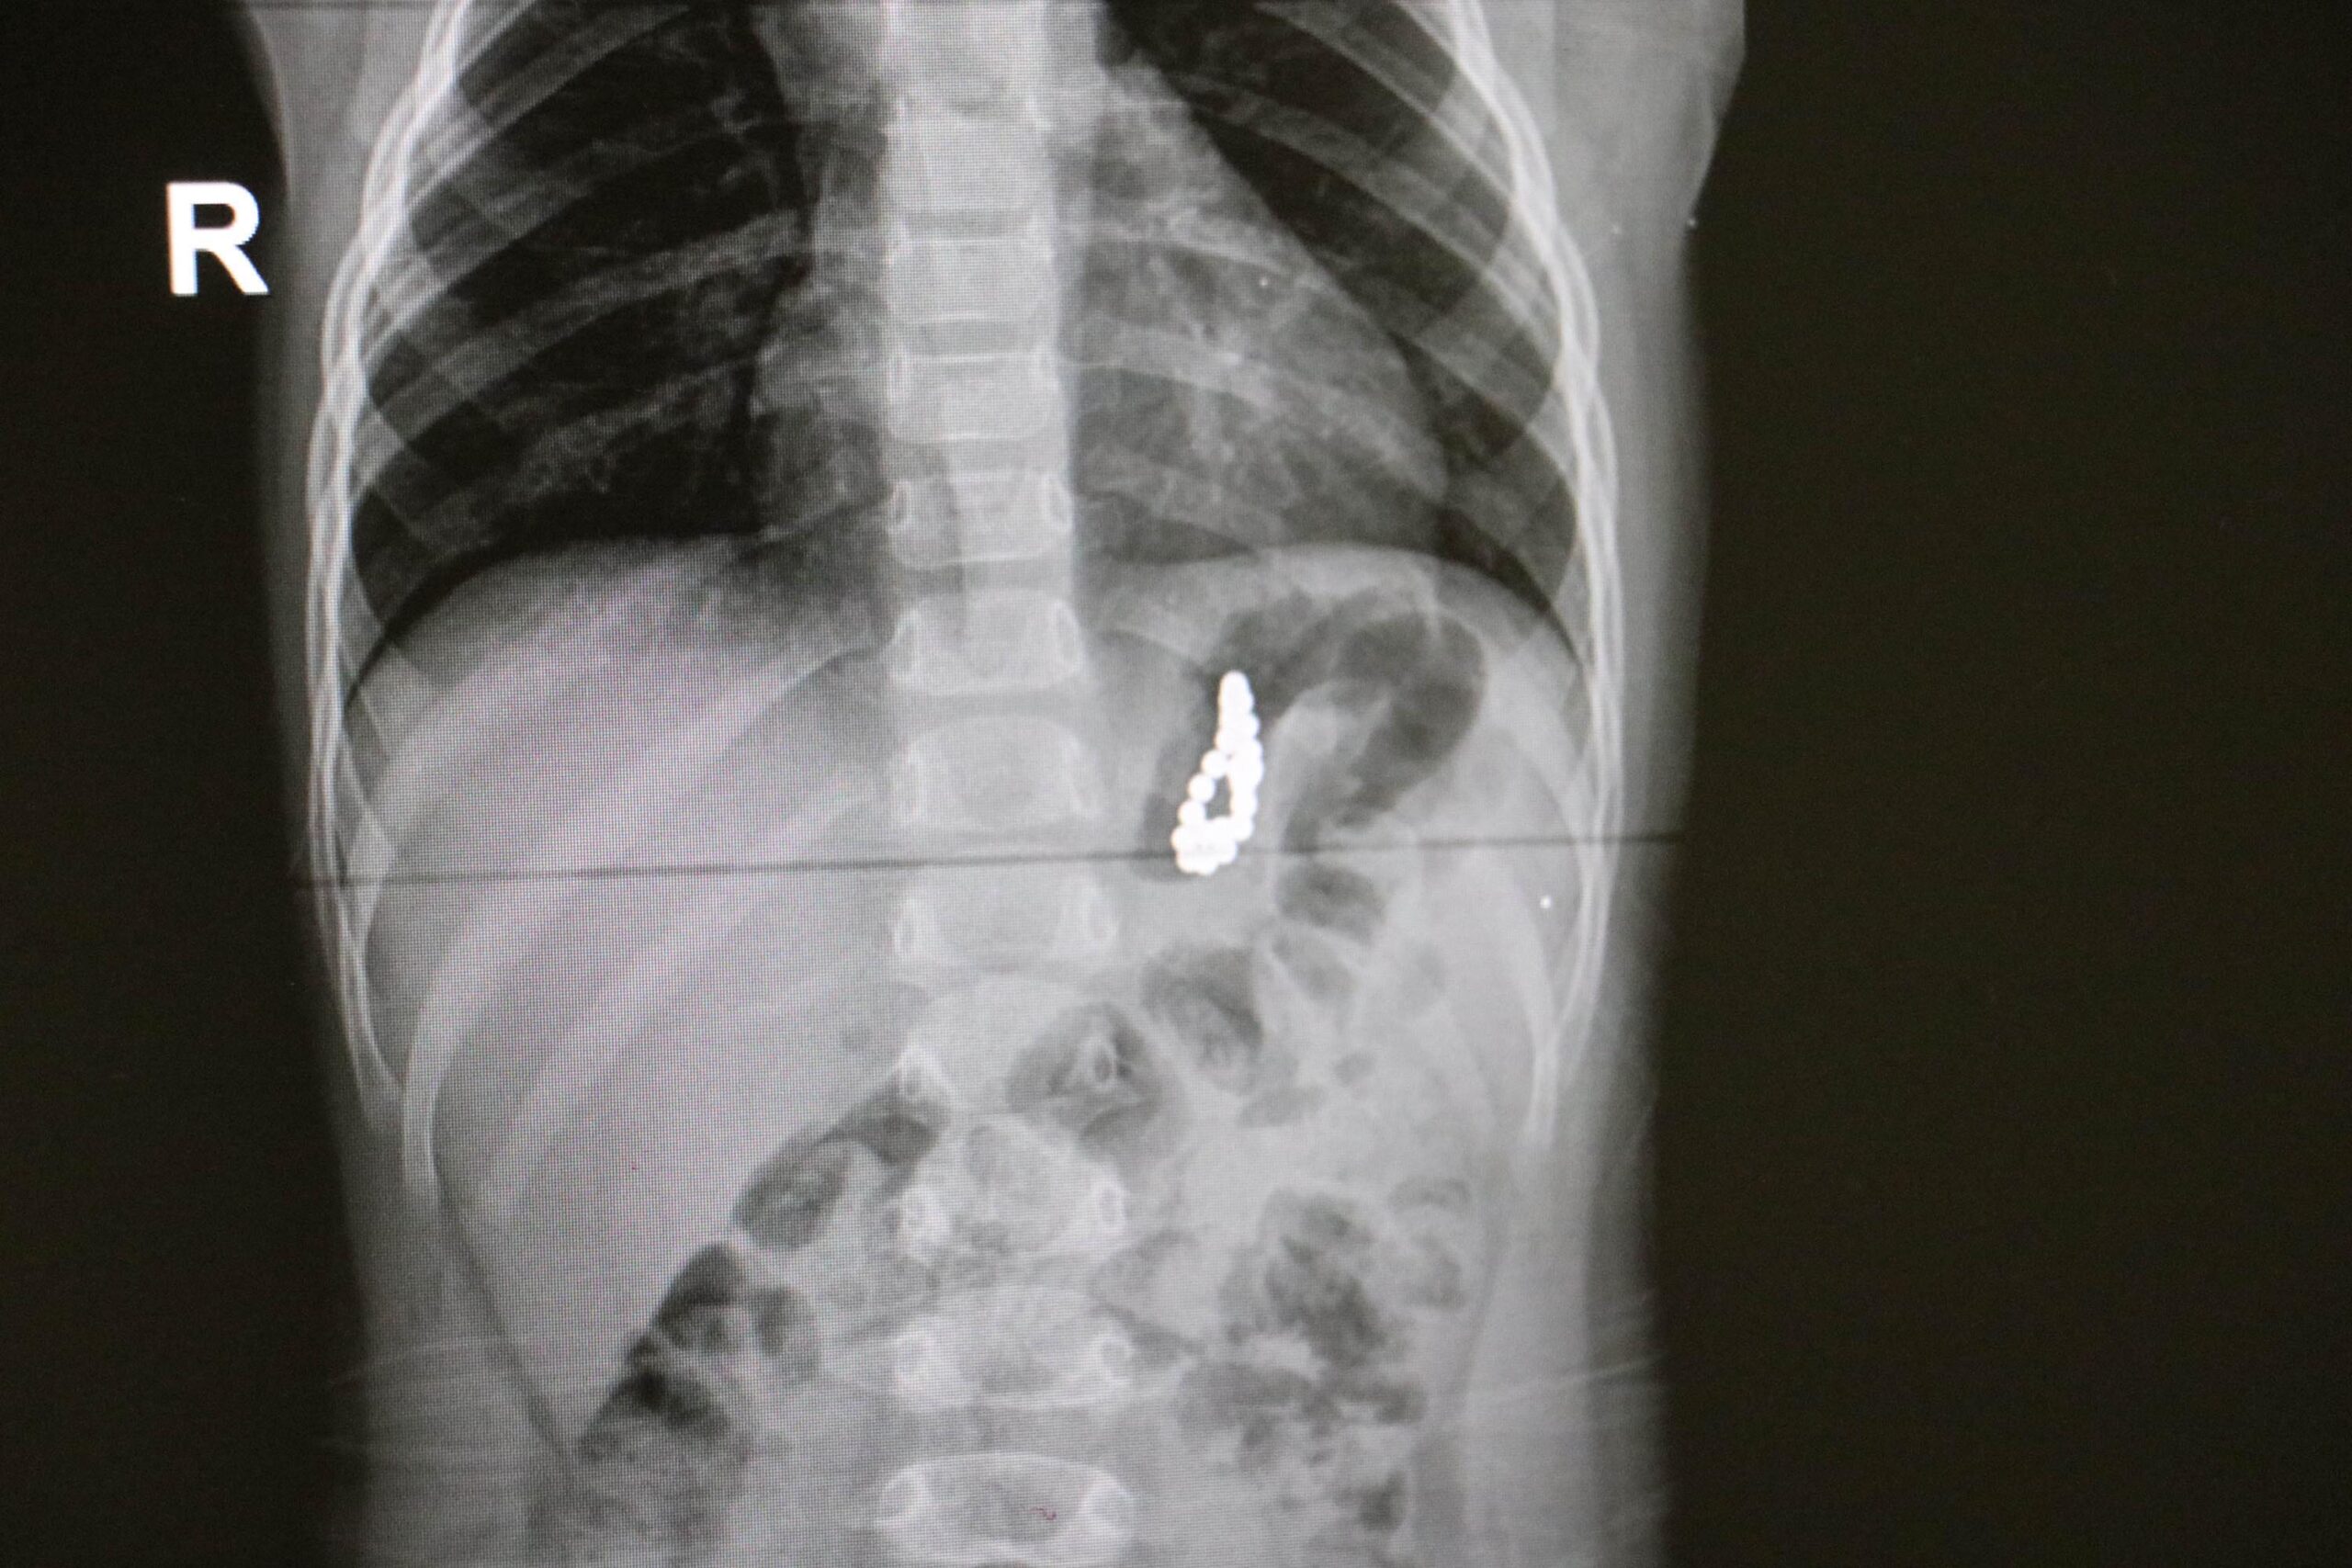

19 aylık bebeğin midesinden 17 mıknatıs çıktı

Denizli'de 19 aylık Murat Özdemir'in midesinden, birbirine yapışık halde 17 adet mıknatıs çıkarıldı.

DHA’da yer alan habere göre, Pamukkale ilçesinde yaşayan Murat Özdemir adlı bebek, geçen hafta aniden rahatsızlanınca kentteki özel bir hastaneye götürüldü. Çekilen röntgende, bebeğin midesinde çok sayıda yabancı cisim bulunduğu belirlendi. Ailesinin Pamukkale Üniversitesi Hastanesi’ne götürdüğü Murat Özdemir, tedaviye alındı. Yapılan tetkikler sonucu, Murat bebeğin çok sayıda mıknatıs yuttuğu tespit edildi. Çocuk Gastroenteroloji Öğretim Üyesi Doç. Dr. Halil Kocamaz tarafından ameliyata alınan Murat Özdemir’in midesindeki 5 milimetre boyutunda 17 adet mıknatıs operasyonla çıkarıldı. Bebeğin yuttuğu mıknatısların yapışarak bilezik şeklini aldığı ve mideyi deldiği belirlendi. Özdemir’in Pamukkale Üniversitesi Hastanesi’ndeki tedavisi devam sürüyor.

Doç. Dr. Kocamaz, hastanın midesinden yabancı cisimleri endoskopi yöntemiyle çıkarttıklarını belirterek, “Yabancı cisimlerin boncuk benzeri mıknatıslar olduğunu gördük. Ameliyatta çıkarmak için kullandığımız aletlere de şiddetli bir şekilde yapıştı. Cisimlerin midenin içini delerek gömüldüğünü fark ettik. Başarılı bir operasyonla mıknatısları mideden çıkardık” dedi.